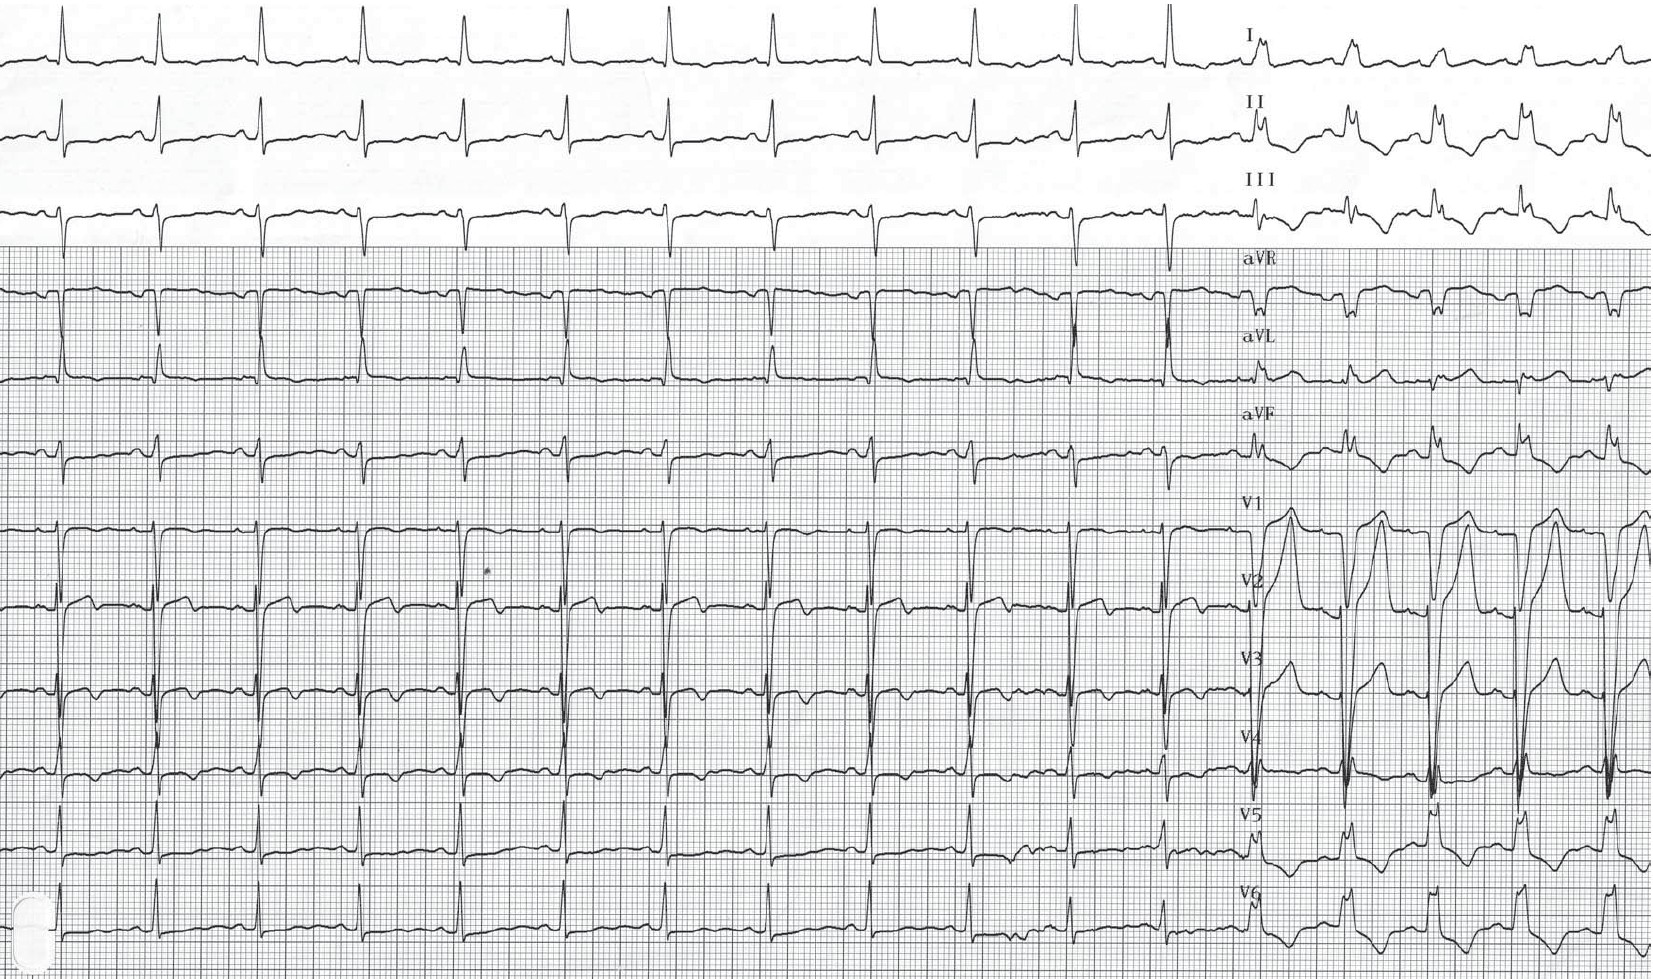

Tracé inverse; à la faveur d’un léger ralentissement, disparition de l’aspect de bloc de branche gauche et retour des QRS fins;

Cette jeune patiente présentait des douleurs thoraciques typiques en l’absence d’antécédent notable ou de facteurs de risque. Ces douleurs apparaissaient pour des efforts relativement modestes. L’électrocardiogramme réalisé au repos montrait des complexes QRS fins de morphologie et de durée normales, une repolarisation sans anomalie. Un électrocardiogramme d’effort a été enregistré avec mise en évidence pour une augmentation limitée de la fréquence cardiaque, d’un aspect de bloc de branche gauche typique contemporain de la survenue de la douleur. A l’arrêt de l’effort, la normalisation du tracé s’accompagnait de la disparition de la douleur. L’échographie cardiaque était normale. Une coronarographie mettait en évidence des artères coronaires saines sans possibilité de déclencher un spasme.